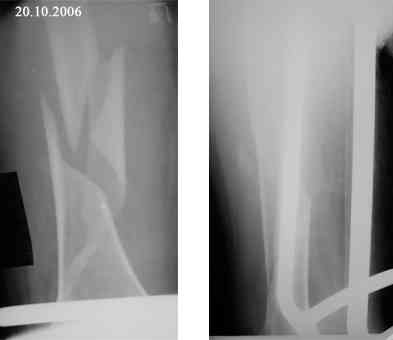

Представляю вашему вниманию снимки в динамике